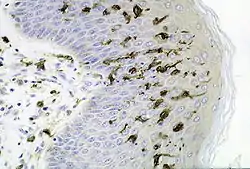

![]() Section of skin showing large numbers of Langerhans cells in the epidermis. (M. ulcerans infection, S100 immunoperoxidase stain.) | |